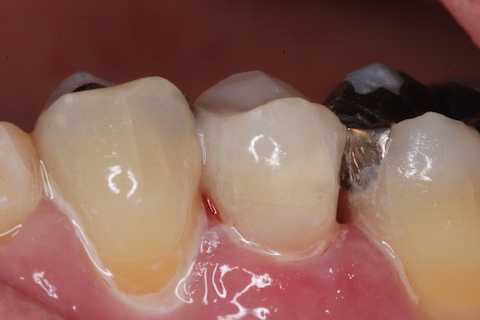

今日の充填治療55(遠心隣接面カリエス) 2023.12.21